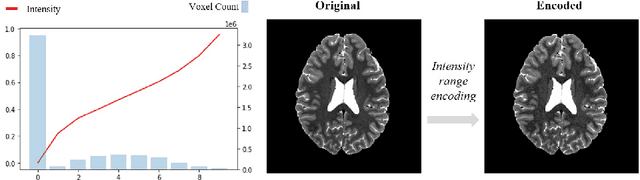

Abstract:Unsupervised Anomaly Detection (UAD) techniques aim to identify and localize anomalies without relying on annotations, only leveraging a model trained on a dataset known to be free of anomalies. Diffusion models learn to modify inputs $x$ to increase the probability of it belonging to a desired distribution, i.e., they model the score function $\nabla_x \log p(x)$. Such a score function is potentially relevant for UAD, since $\nabla_x \log p(x)$ is itself a pixel-wise anomaly score. However, diffusion models are trained to invert a corruption process based on Gaussian noise and the learned score function is unlikely to generalize to medical anomalies. This work addresses the problem of how to learn a score function relevant for UAD and proposes DISYRE: Diffusion-Inspired SYnthetic REstoration. We retain the diffusion-like pipeline but replace the Gaussian noise corruption with a gradual, synthetic anomaly corruption so the learned score function generalizes to medical, naturally occurring anomalies. We evaluate DISYRE on three common Brain MRI UAD benchmarks and substantially outperform other methods in two out of the three tasks.